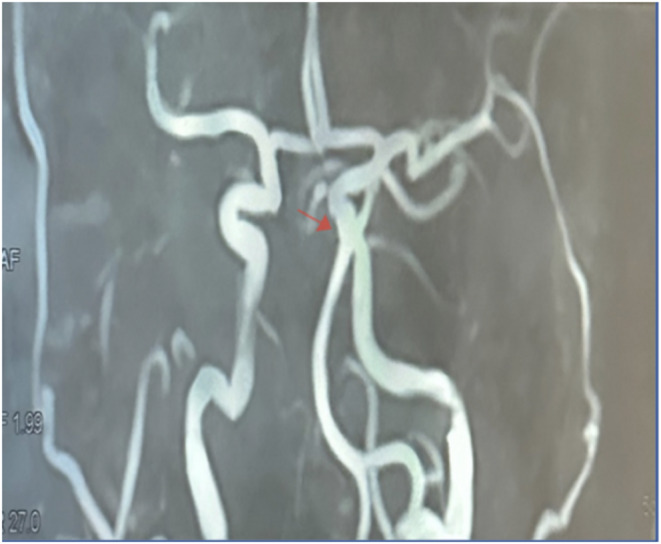

Introduction: Hemifacial spasm (HFS) is a neurological disorder characterized by involuntary contractions of the facial muscles. Botulinum toxin (BTX-A) is an effective treatment, but its efficacy may vary across different geographical contexts. This multicentric study aims to compare the efficacy of BTX-A in treating HFS between centers in Morocco and France.

Methods: A retrospective study was conducted with 128 patients diagnosed with HFS, distributed between one center in Morocco and two centers in France. Parameters studied included age, sex, average treatment duration, dose administered, injection sites, injection frequency, and adverse effects. The results were analyzed separately for primary and secondary HFS. An HSF-8 score was used to evaluate treatment outcomes, assessing patients before treatment and two months after receiving BTX-A injections.